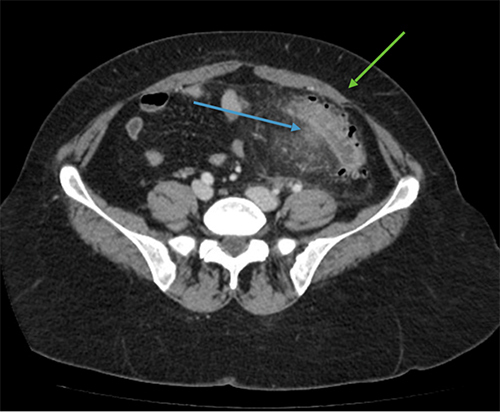

Le diagnostic est tout à fait possible, à évoquer ici en première intention devant l’âge (> 40 ans) et la symptomatologie (douleurs fébriles en fosse iliaque gauche et hypogastre).

– de la localisation de la douleur en fosse iliaque gauche ;

– du syndrome inflammatoire : fièvre à 38,5 °C avec hyperleucocytose à la biologie ;

– de l’argument de fréquence de cette pathologie à cet âge (la prévalence des diverticules sigmoïdiens est de plus en plus importante avec l’âge, après 40 ans).